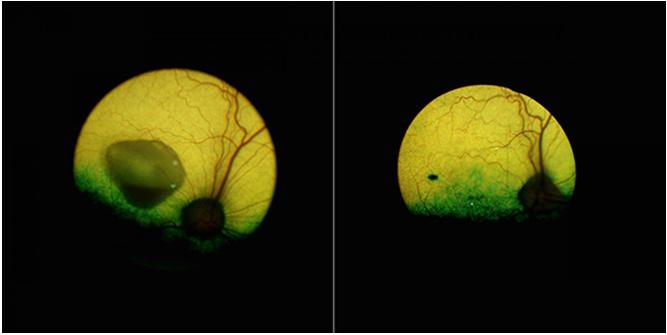

卵黄状黄斑变性犬的眼睛,左侧是未治疗的,右侧是基因治疗5年后的。来源:宾夕法尼亚大学

更令人鼓舞的是,经过治疗的狗狗的眼睛在长达5年的时间里都没有疾病。这种基因疗法在狗身上是有效的。“在分子水平上,我们证实了犬类和人类的BEST1基因都能纠正RPE-PR复合物的位置,并可以恢复这个关键接口的细胞结构”,Cideciyan说。